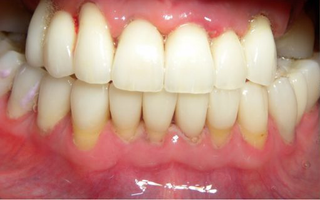

Implants today can provide solutions to problems that in days gone by were unsalvageable. Many people with missing teeth were faced with no alternative to removable full or partial dentures. In instances of single missing teeth, people have had no choice but to bridge the space [fixed option] or wear a removable denture. Now with implant dentistry being widely practiced in mainstream dentistry we have elegant solutions to overcome these problems.

A dental implant is an artificial replacement for a missing tooth root. The implant fixture [fabricated out of titanium] is placed surgically into the bone and allowed to heal and integrate. Because the implant surface is not recognized by the body as being a foreign object the bone heals around the fixture. This relationship then allows the restoring dentist to place crowns or bridgework or dentures on top of this artificial root.

- Improved appearance

- Improved comfort and speech

- Ability to eat whatever you want

- Smile with confidence

- Maintain healthy adjacent teeth

- Long term results

- Maintenance of bone